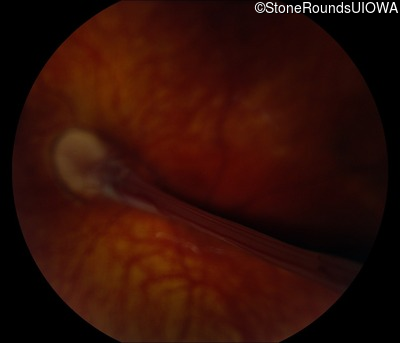

AD Familial Exudative Vitreoretinopathy (IIIE2b)

Age at visit: 23 months

This 23 month old male has had nystagmus since shortly after birth. He was born at term (7lbs 12oz).